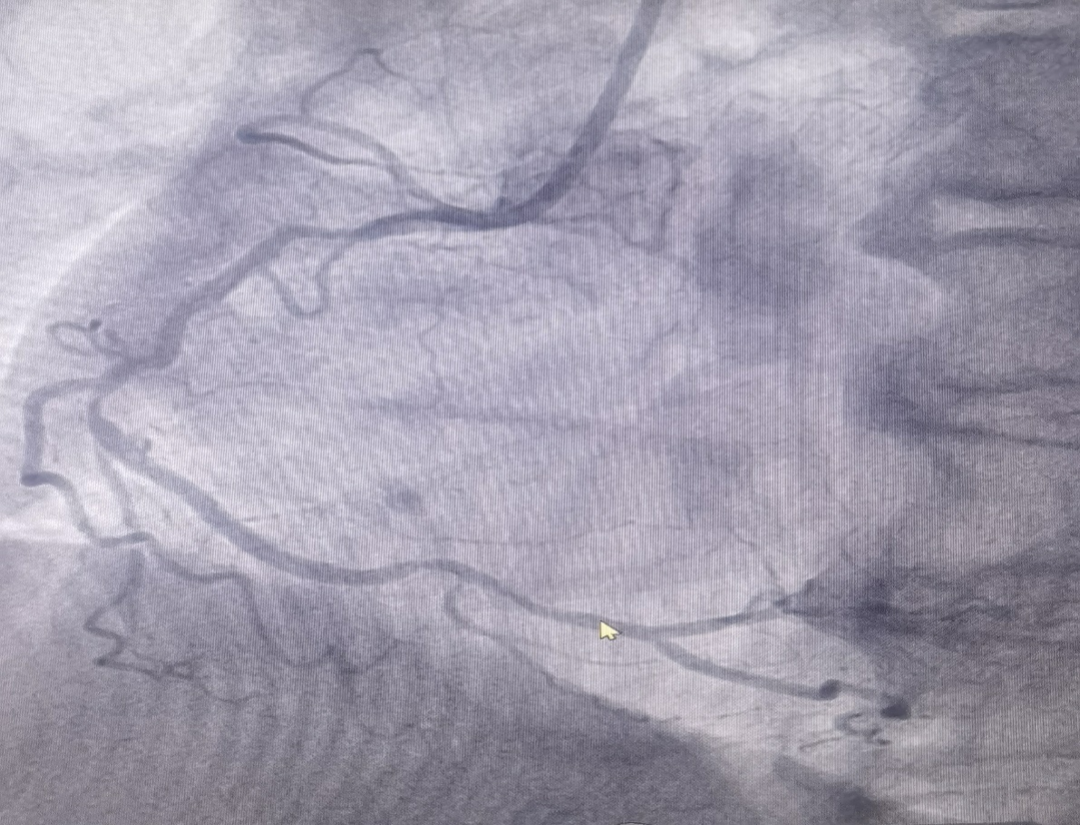

男性患者,72歲,入院診斷為:冠心病,不穩定型心絞痛。冠脈造影結果提示右冠脈重度狹窄,考慮為此次發病的病變血管。

(圖為右冠病變術前影像)